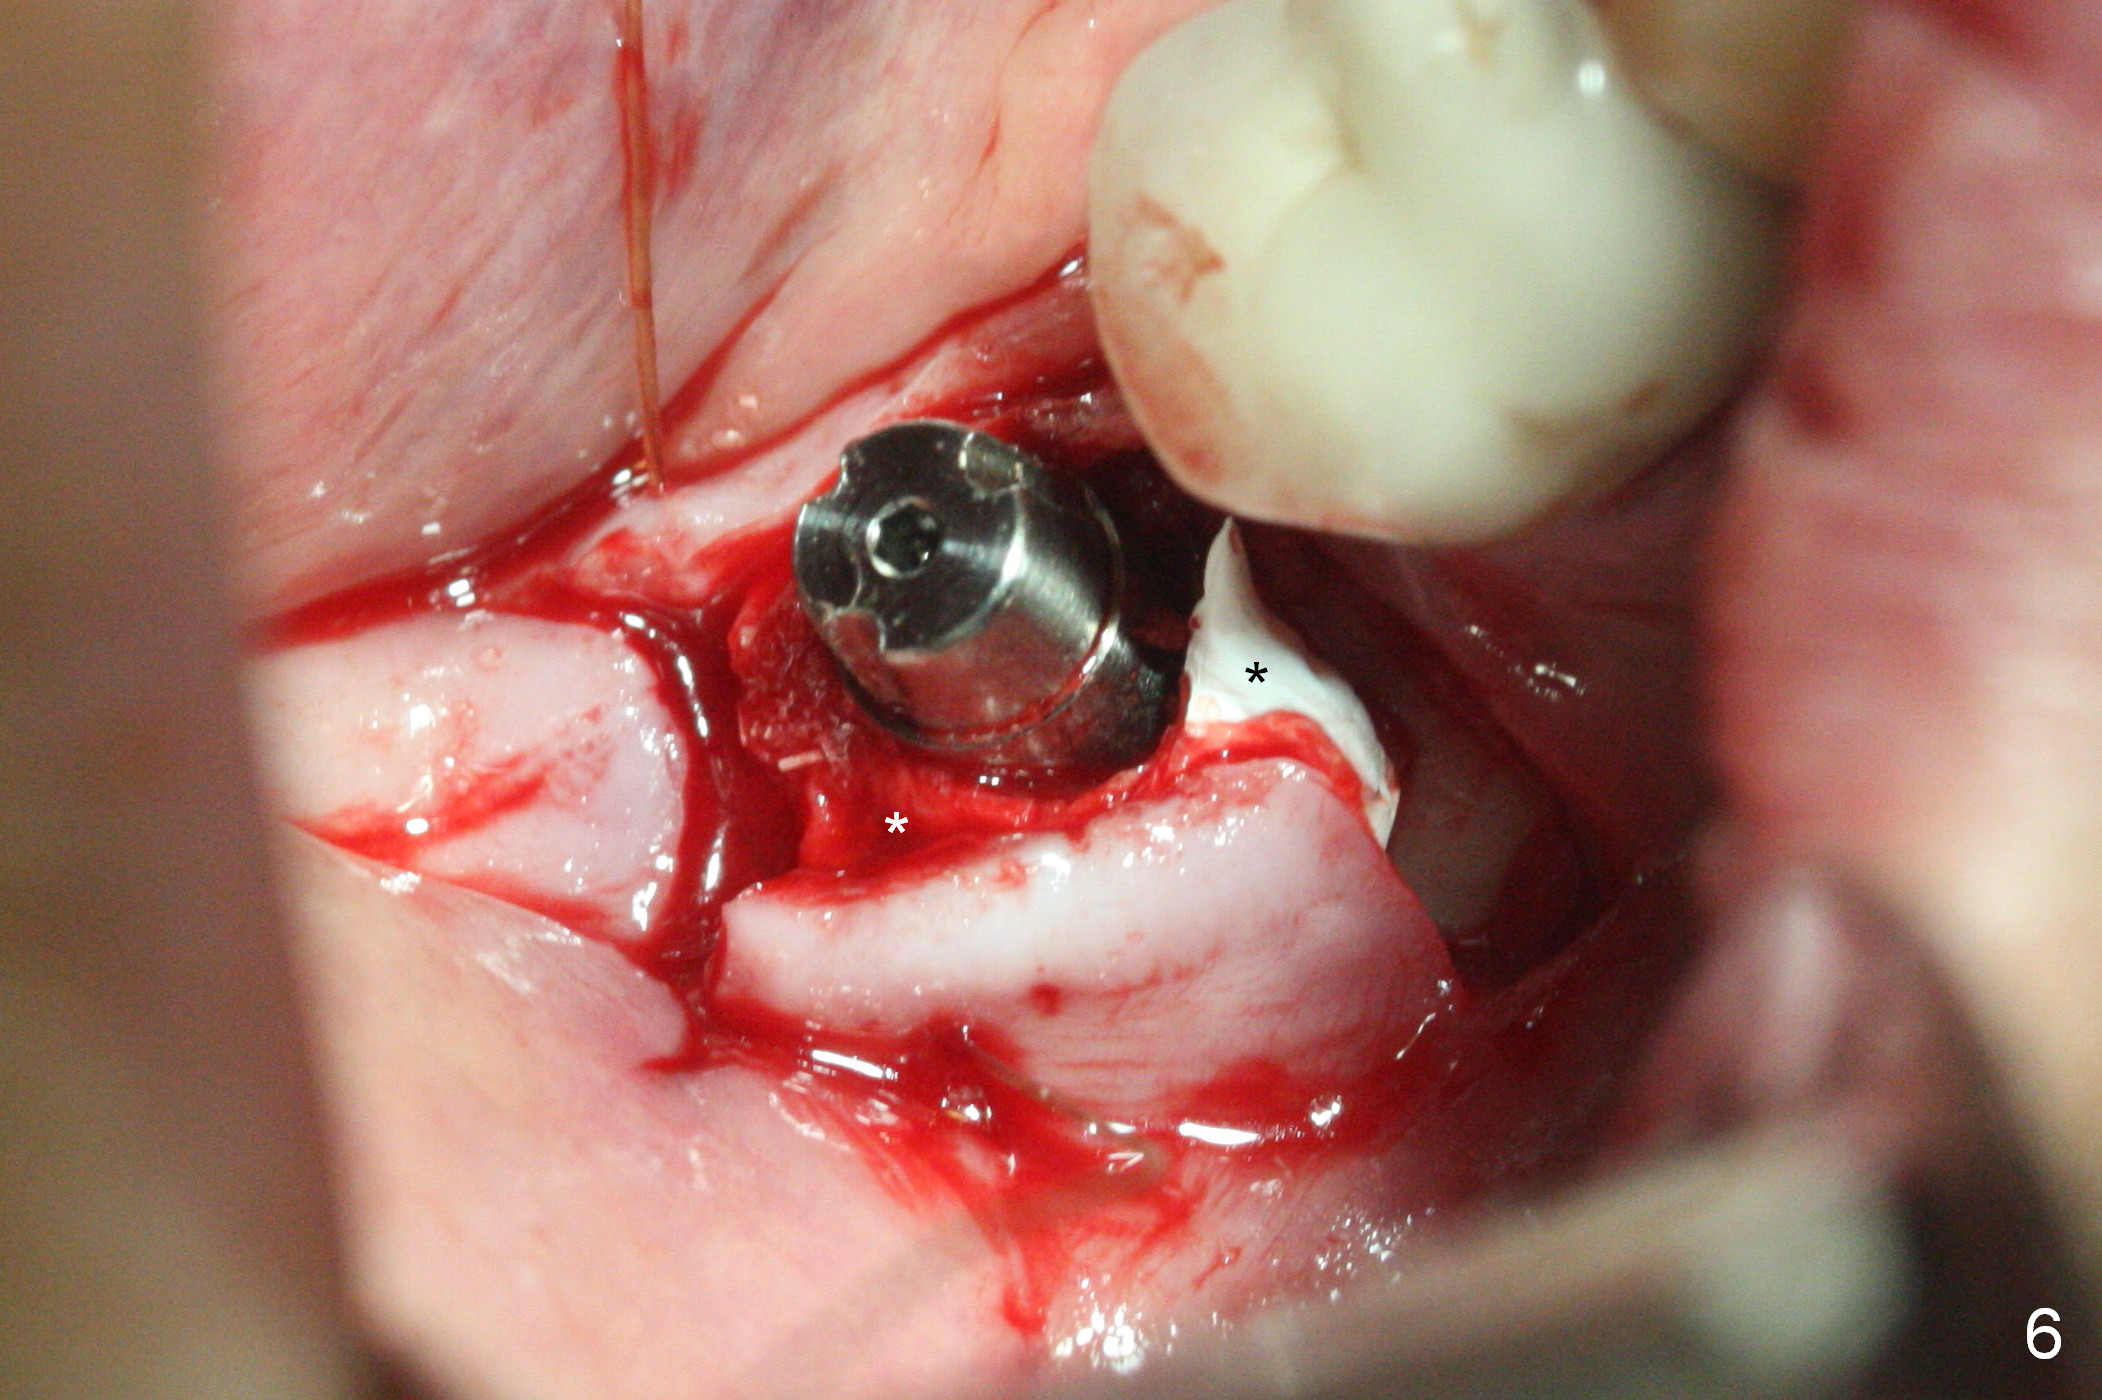

Initial osteotomy at the site of #31 using 2 mm pilot drill for 11 mm appears to be distal by 2-3 mm (Fig.1, Fig.10 A (circle, occlusal view of the edentulous and dentate (#29 and 30) areas)). Lindamann bur is used to move the osteotomy (Fig.8 white rectangle, Fig.10 B). It seems that the osteotomy returns distal as the osteotomy increases (Fig.2 (5x17 mm tap), Fig.8 arrow, Fig.10 C (green circle)). It appears to be late to change; a 5x17 mm tissue-level implant is placed with > 60 Ncm (Fig.3-5). The buccal and lingual rough surface of the implant (Fig.5 *) is covered by autogenous bone/Osteogen and Collagen Dressing (Fig.6 *). After suturing (Fig.7), periodontal dressing is applied around the abutment (Fig.5 A (4.5x3 mm)).